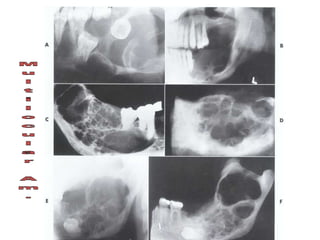

Ameloblastoma

Large multilocular soap bubble appearance.

Typically located in the molar region, angle of the

mandible and ascending ramus

Thin not penetrated cortical plate.

Impacted or neighboring teeth are displaced with

roots often resorped.